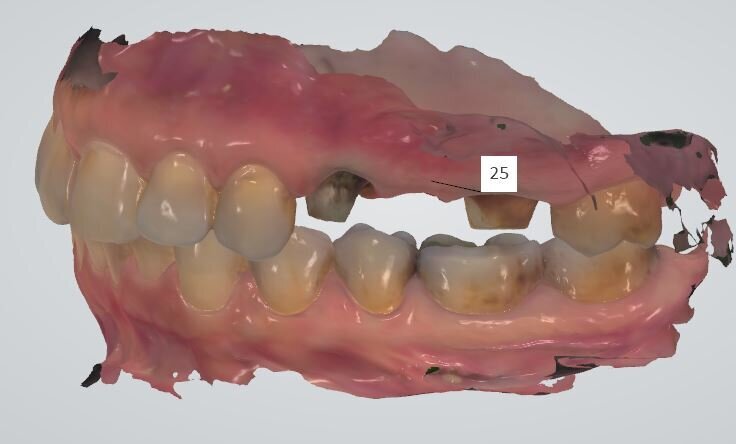

La terapia endodontica estesa agli elementi adiacenti ha consentito di eseguire un provvisorio che ha permesso alla paziente di non subire il disagio estetico e funzionale del mancato carico dell’impianto. Dopo due mesi si è provveduto a rilevare le impronte per la riabilitazione finale. Abbiamo utilizzato un sistema digitale (Trios-Trishape) che seguendo la procedura di lettura rileva le varie impronte dal provvisorio, al tragitto transmucoso, in tal caso è necessario provvedere a posizionare i fili retrattori che siamo soliti utilizzare nella lettura del finish line e solo al momento della lettura andiamo a rimuovere il 2° filo e a svitare la vite di guarigione o il moncone provvisorio così da non determinare il collasso dei tessuti del tragitto transmucoso implantare (Fig. 6). Dopo l’impronta dei tessuti e dei monconi degli elementi naturali si procede a segnalare gli elementi da protesizzare (Fig. 7) e successivamente si posiziona il transfer dell’impianto che nel sistema digitale è rappresentato dallo scan body o corpo di scansione (Fig. 8).

Lo scan body è solitamente caratterizzato da un materiale non riflettente come il Peek e da una semplicità geometrica come un cilindro con una faccetta piatta che rappresenta la posizione spaziale dell’impianto stesso, sarà poi l’algoritmo a cui è riferito nella banca dati del software a determinare la precisione dell’impronta stessa. Bisogna rammentare che tale procedura non dipende solo dalla sistematica impiantare, ma anche dallo scanner intraorale utilizzato nella registrazione dell’impronta (IOS Intra Oral Scanner). Al termine della ripresa è possibile visualizzare sullo schermo anche questo passaggio (Fig. 9), dopodiché si passa al rilevamento della posizione di centrica (Fig. 10).

Fig. 7 - La schermata dell’impronta rilevata con sistema IOS Trishape.

Fig. 9 - Stessa schermata con lo scan body e con la numerazione degli elementi selezionati per la realizzazione protesica definitiva.